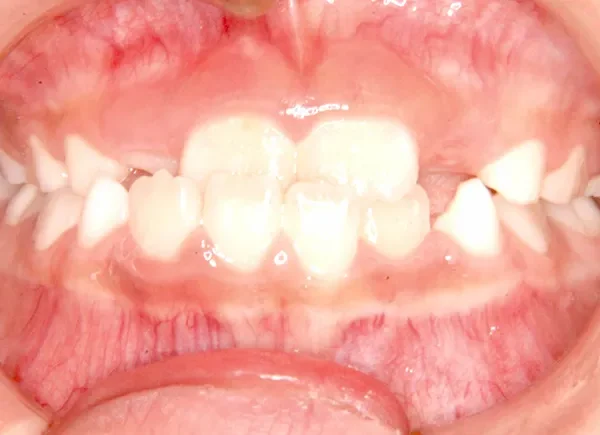

【子供の矯正(一期)】叢生・反対咬合・受け口・非抜歯症例・7歳女児【M.H様】

初診時年齢 小学校1年生 (女性) 主訴 受け口

診断名 叢生・反対咬合 装置名

状態 永久歯が生える隙間がない(叢生)

受け口(下顎前突/反対咬合)

下顎が大きい傾向があります。

上下の真ん中にズレがあるのと、上下とも永久歯の生えるスペースがせまいため、オリジナル矯正装置でスペースを作り、受け口も改善していきます。

初診